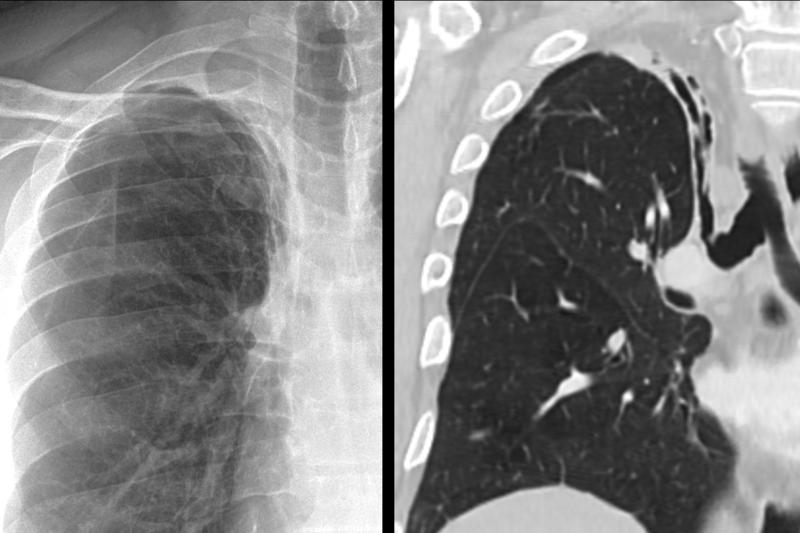

RUL collapse Case 11